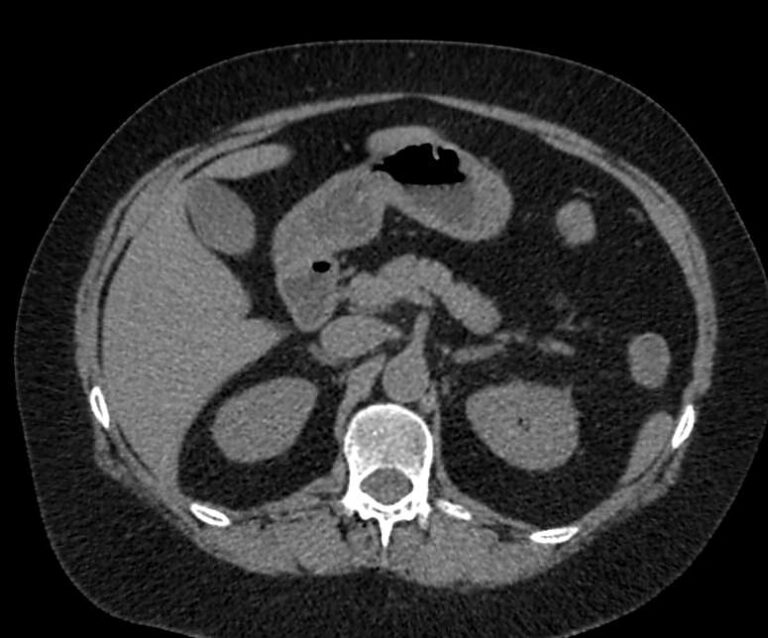

Мультиспиральная компьютерная томография (МСКТ) брюшной полости относится к современным лучевым методам исследования, с помощью которого можно оценить состояние органов брюшной полости (печени, желчного пузыря, поджелудочной железы, селезенки), прилегающих к ним кровеносных сосудов и лимфатических узлов.

С помощью мультиспиральной компьютерной томографии проводятся послойные рентгеновские снимки исследуемой области с толщиной среза от 0,5 мм. В нашей клинике исследование выполняется на компьютерном томографе экспертного класса TOSHIBA AQUILION CXL, который оснащен 128 детекторами, позволяющими получать за несколько секунд снимки брюшной полости с высокой точностью. Большое количество детекторов позволяет получить точные данные, при этом сократить время исследования и сделать минимальной лучевую нагрузку на пациента. Кроме того, инновационные технологии аппарата дают возможность сформировать объемную модель органа и окружающих структур, что также способствует проведению точной и достоверной диагностики.

При подозрении на опухоли, воспалительные процессы, гнойные очаги назначается КТ брюшной полости с внутривенным болюсным контрастированием. Для этого пациенту внутривенно вводится рентгеноконтрастное вещество на основе йода. Благодаря усиленному кровоснабжению препарат накапливается в структуре патологических образований и помогает врачу-рентгенологу выявить изменения в структуре внутренних органов.

Метод контрастирования помогает максимально точно выявить очаг патологии уже на начальной стадии, а также установить его локализацию, точные размеры, форму и особенности кровоснабжения.